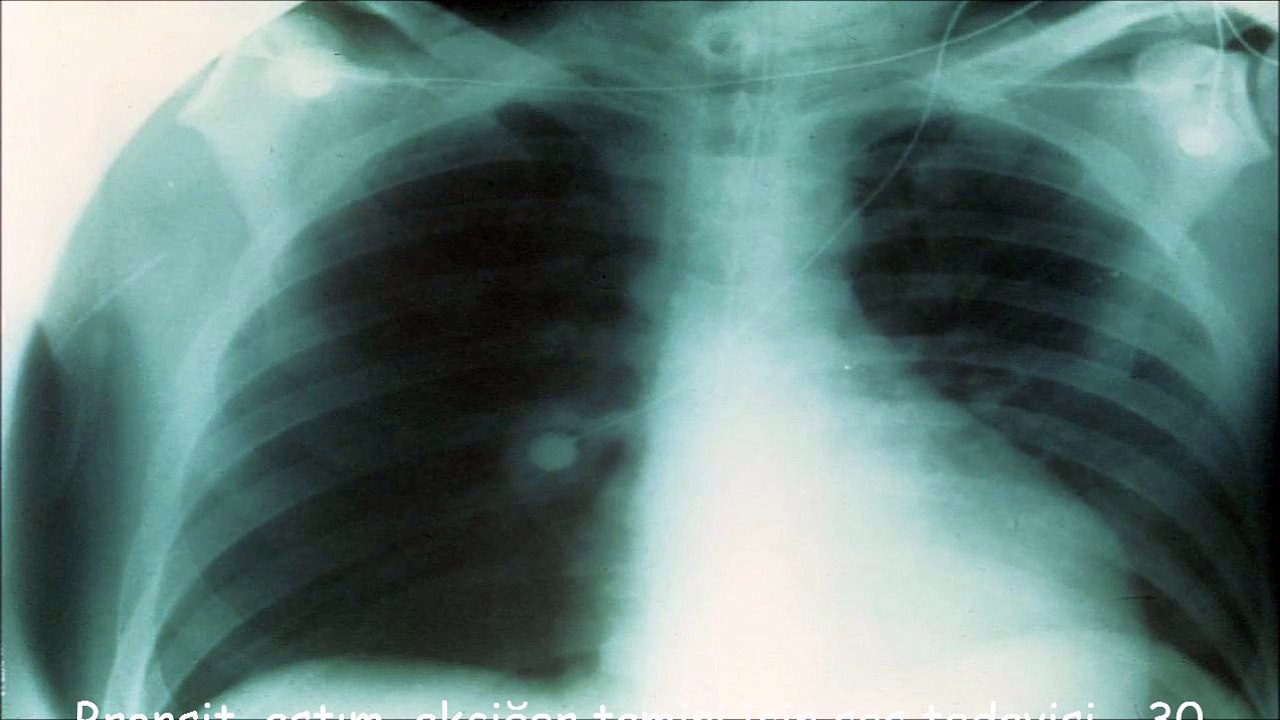

Bronşit, astım, akciğer tamiri için ses tedavisi - 30 dakika